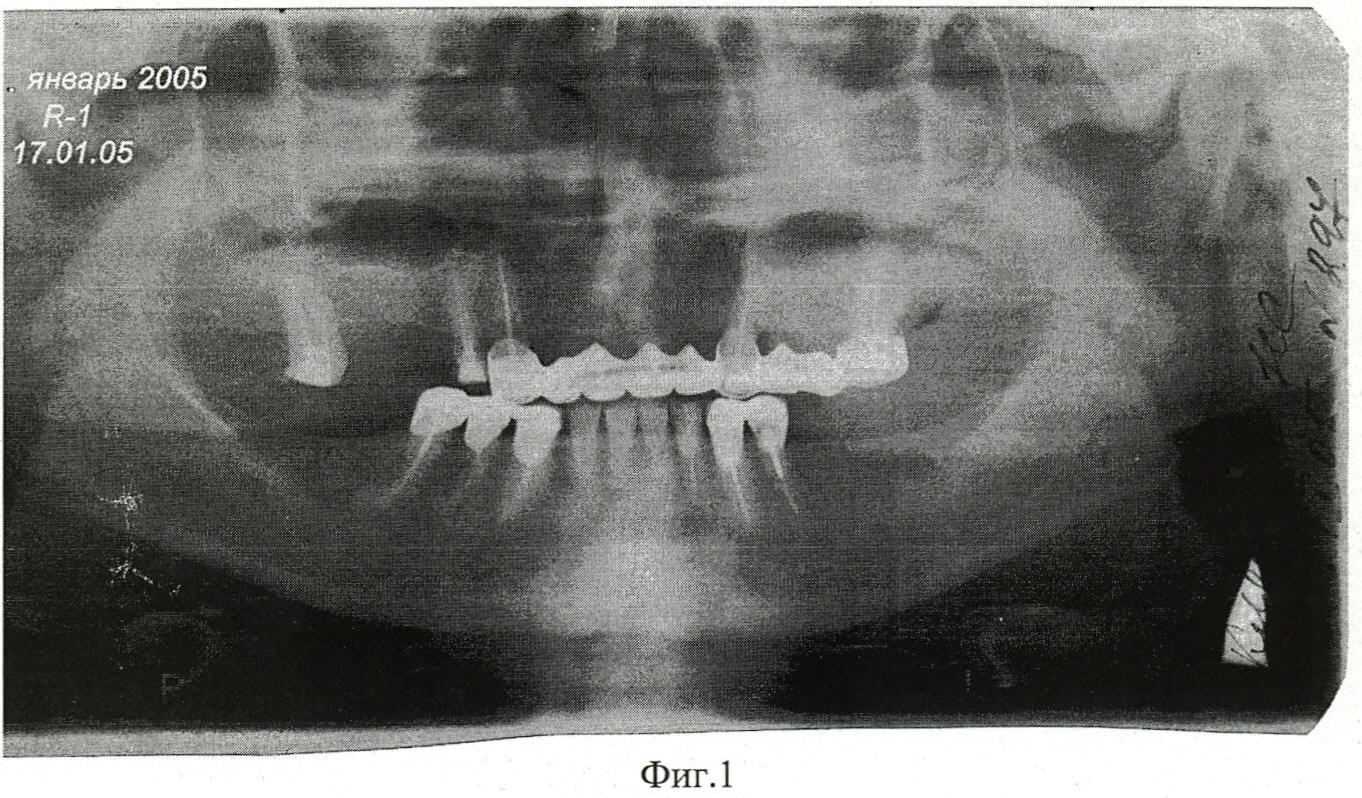

Фиг.1 – Панорамная рентгенограмма больной К. с хроническим деструктивным периодонтитом 23 зуба, до лечения.

Пациентка К., 62 года, поступила в клинику ИСЦ «НАНО-ДЕНТ» с диагнозом хронический деструктивный периодонтит 23 зуба (см. Фиг.1).

Рентгенографические обследования больной показали восстановление костной ткани вокруг корня 23 зуба через 3 месяца после инъекции (см. Фиг.3)и через 2,5 года, (см. Фиг.4).